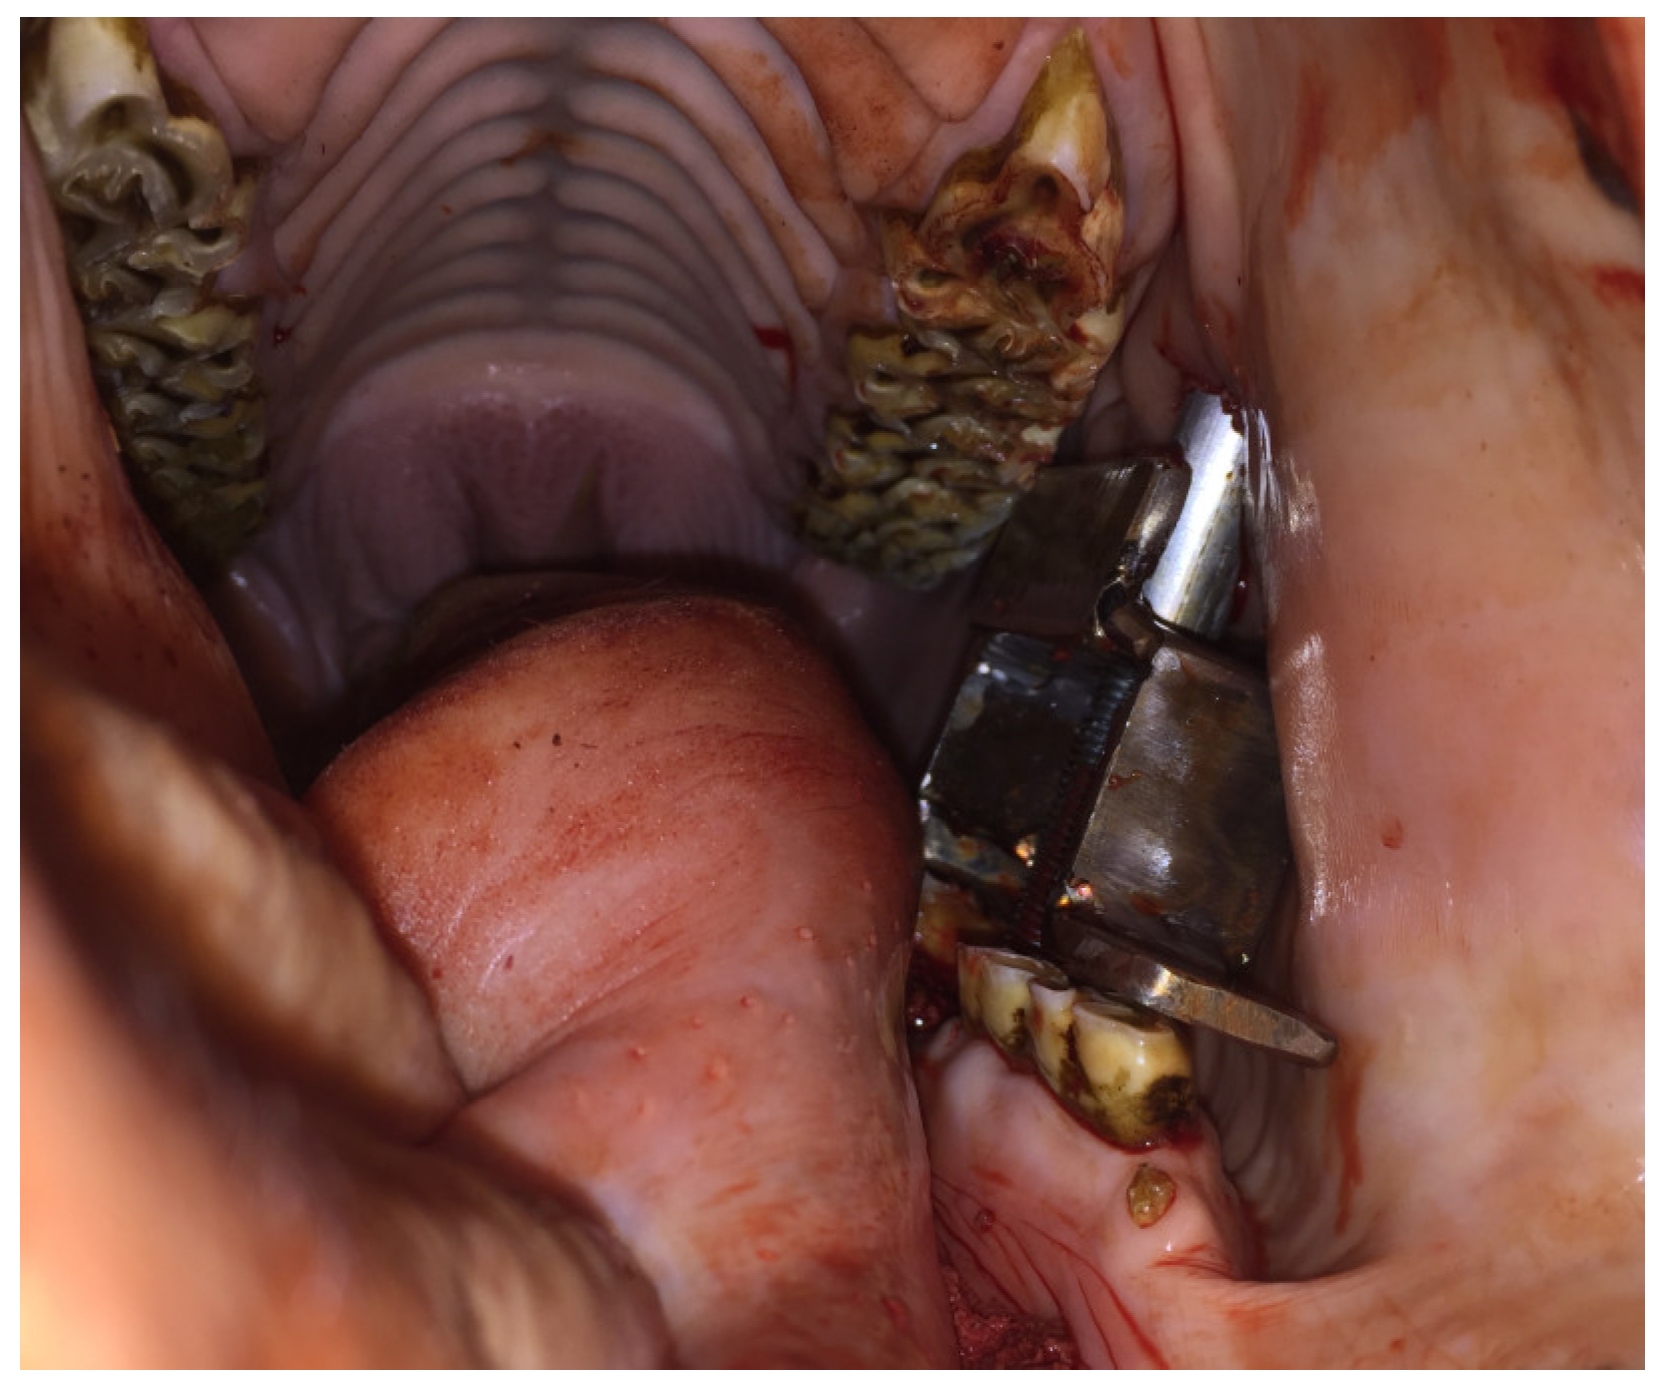

Figure 4.

Image of the CSET device being used to extract a 307 tooth in one of the cadaver’s heads. Drilling the tooth longitudinally was difficult, and the crown fractured during the extraction.